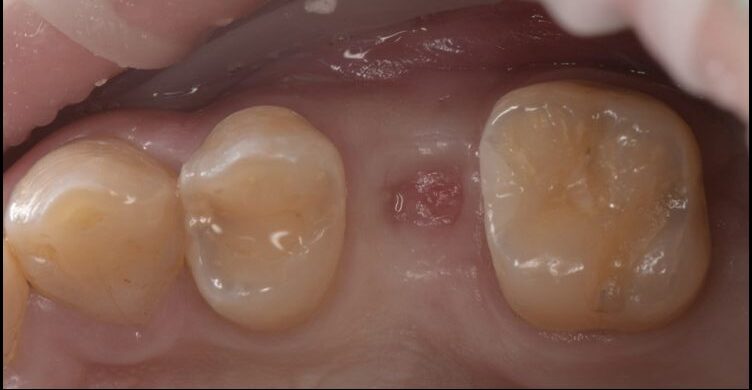

欠損した歯をインプラントで治療した症例

Before

After

| 治療内容 | インプラント治療 |

| 治療期間・治療回数 | 2ヶ月半 |

| 治療費用 | 528,000円(税込) |

| リスク・副作用 | 外科処置を伴います。 |

| 備考 | 治療方法や費用、治療期間などは、ケースによって異なります。患者さまに合わせた治療計画をカウンセリング時にご提案いたしますので、治療例は参考程度にご覧ください。 |